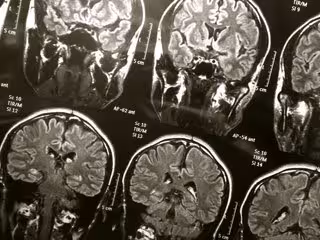

Detectan infecciones causadas por hongos en cerebros de pacientes fallecidos con Alzheimer

Cerebro

FLICKR/WYINOUE